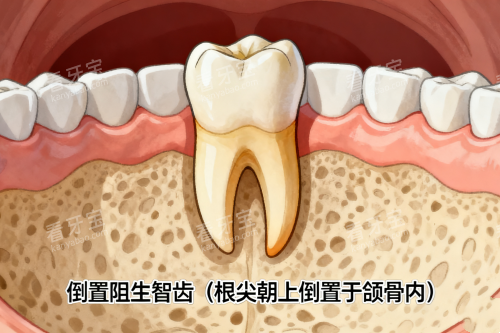

我先简单说了下智齿的情况。她没急着下结论,而是先让我躺下,做了一次齐全的口腔检查。用的是一次性的口镜和探针,这个细节让人安心。她一边看,一边会同步告诉我她看到的情况:“你这颗智齿长得有点歪,和前面的牙齿形成了一个小凹槽,平时容易藏东西,自己可能不好清洁……这边有颗大牙,咬合面看到有个非常小的黑点,我轻轻探一下,你感觉酸吗?不酸?那可能只是色素沉着,但我们可以定期观察……”

整个过程大约持续了十几分钟。她不仅看了我主诉的智齿,还仔细检查了每一颗牙的牙面、牙龈状况,甚至简单看了下我的咬合关系。结束后,她让我坐起来,走到一旁的电脑前调出刚才拍摄的影像(一种小范围的X光片),指着屏幕上的影子,开始解释。

2. 沟通:方案与选择权

关于智齿,她的分析很直接:“从片子上看,牙根形态还算规整,但完全埋在牙龈下面,顶到了前面的牙。现在虽然没有急性发炎,但长期来看,清洁不到位可能引发前面那颗好牙的蛀牙,或者导致牙龈反复发炎。拔除是一个可以考虑的选择。”

她并没有强调“必须立刻拔”,而是列出了几种可能性:如果暂时不想处理,需要特别注意用牙线清洁那个位置;如果选择拔除,大概的流程、时间以及后续需要注意些什么,她都一一说明。尤其提到了拔牙过程中可能会有的一些感觉,以及如何配合能让自己更轻松。